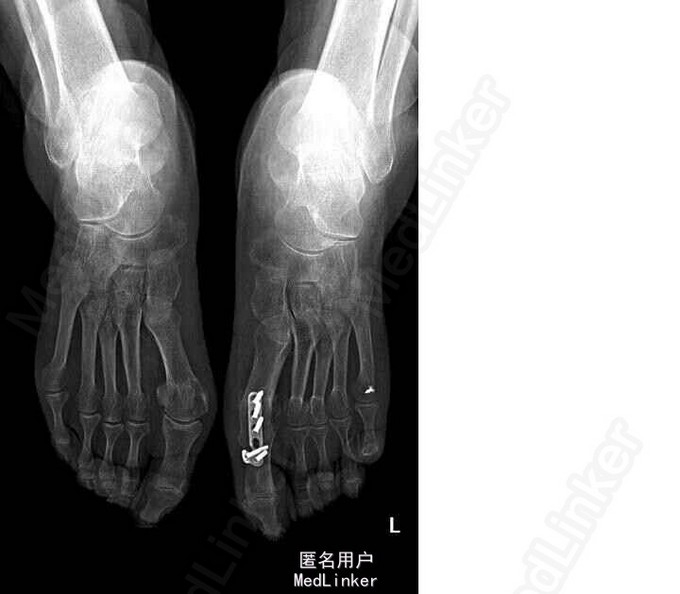

64岁,女性。3年前发现因双侧扁平足,双踇趾外翻,左侧较重,于我院行左足截骨矫形内固定术。1年前感左足踇趾疼痛,诊断为周围神经炎,予以弥可保治疗后感症状缓解。1月后仍感左足踇趾疼痛,行走时加重。

查体:双足呈扁平畸形,负重位足面间距增宽。左踇趾呈锤状趾畸形,活动度差,踇趾外侧有一约5cm手术瘢痕,左足踇趾根部内侧皮肤增厚粗糙,颜色发红,皮肤无破溃。左足底及第5趾外侧可见胼胝增厚。 X光片示扁平足术后改变

诊断:双侧扁平足(左侧重),左足截骨矫形术后,左足第一、五跖趾骨关节炎 局麻下行“左足矫形术(第五趾间关节融合内固定,第一、三、五趾骨屈肌腱松解,第一趾骨伸肌腱紧缩术)”。